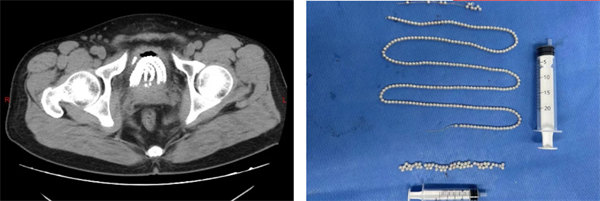

患者男44歲,因不慎將異物塞入尿道后無法自行取出,劇烈疼痛且排尿困難,隨緊急于寶雞市人民醫(yī)院泌尿病院就診。入院后,經(jīng)過詳細(xì)的病史詢問和全面的術(shù)前檢查,泌尿病院專家團(tuán)隊(duì)迅速制定了科學(xué)、合理的手術(shù)方案,決定采用經(jīng)尿道膀胱異物取出術(shù)進(jìn)行治療。

手術(shù)由泌尿病院泌尿外二科副主任杜喬主刀,在麻醉手術(shù)科的緊密配合下,通過先進(jìn)的醫(yī)療設(shè)備和技術(shù)手段,成功將患者膀胱內(nèi)的異物完整取出。術(shù)后,患者恢復(fù)良好,疼痛消失,排尿恢復(fù)正常。

其實(shí)我院接收的膀胱異物患者不在少數(shù),患病人群主要系兒童及男性青壯年;這些異物可能是患者因好奇、不慎、尋求性快感或其他原因塞入尿道的各種物品,如磁珠、鐵絲、縫衣針、電線、橡皮管等。該類患者多因隱瞞病史或延誤治療時(shí)機(jī)而加重病情。異物一旦進(jìn)入尿道后容易嵌頓,難以自行排出。如長時(shí)間不取出,可導(dǎo)致尿頻、尿急、尿痛、血尿、排尿困難等癥狀,甚至導(dǎo)致膀胱結(jié)石的形成,進(jìn)一步加重尿路梗阻和感染的風(fēng)險(xiǎn),嚴(yán)重者引起粘膜壞死、繼發(fā)性狹窄等嚴(yán)重并發(fā)癥。尖銳的異物還有可能戳穿尿道或膀胱壁,危及生命。

圖片